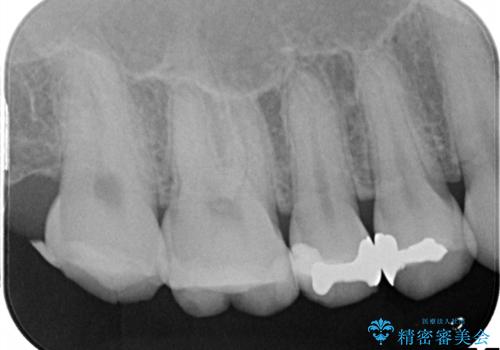

【メタルフリー】銀歯を白くしたい。オールセラミッククラウン。

- 銀歯を白くしたいと希望され来院されました。

すぐにでも白くしたいとのことで、2回目の来院で銀歯を白い仮歯に変更し喜んでいただきました。

ただ単純に白くするでけではなく拡大鏡を使用し、丁寧な処置を行なっております。